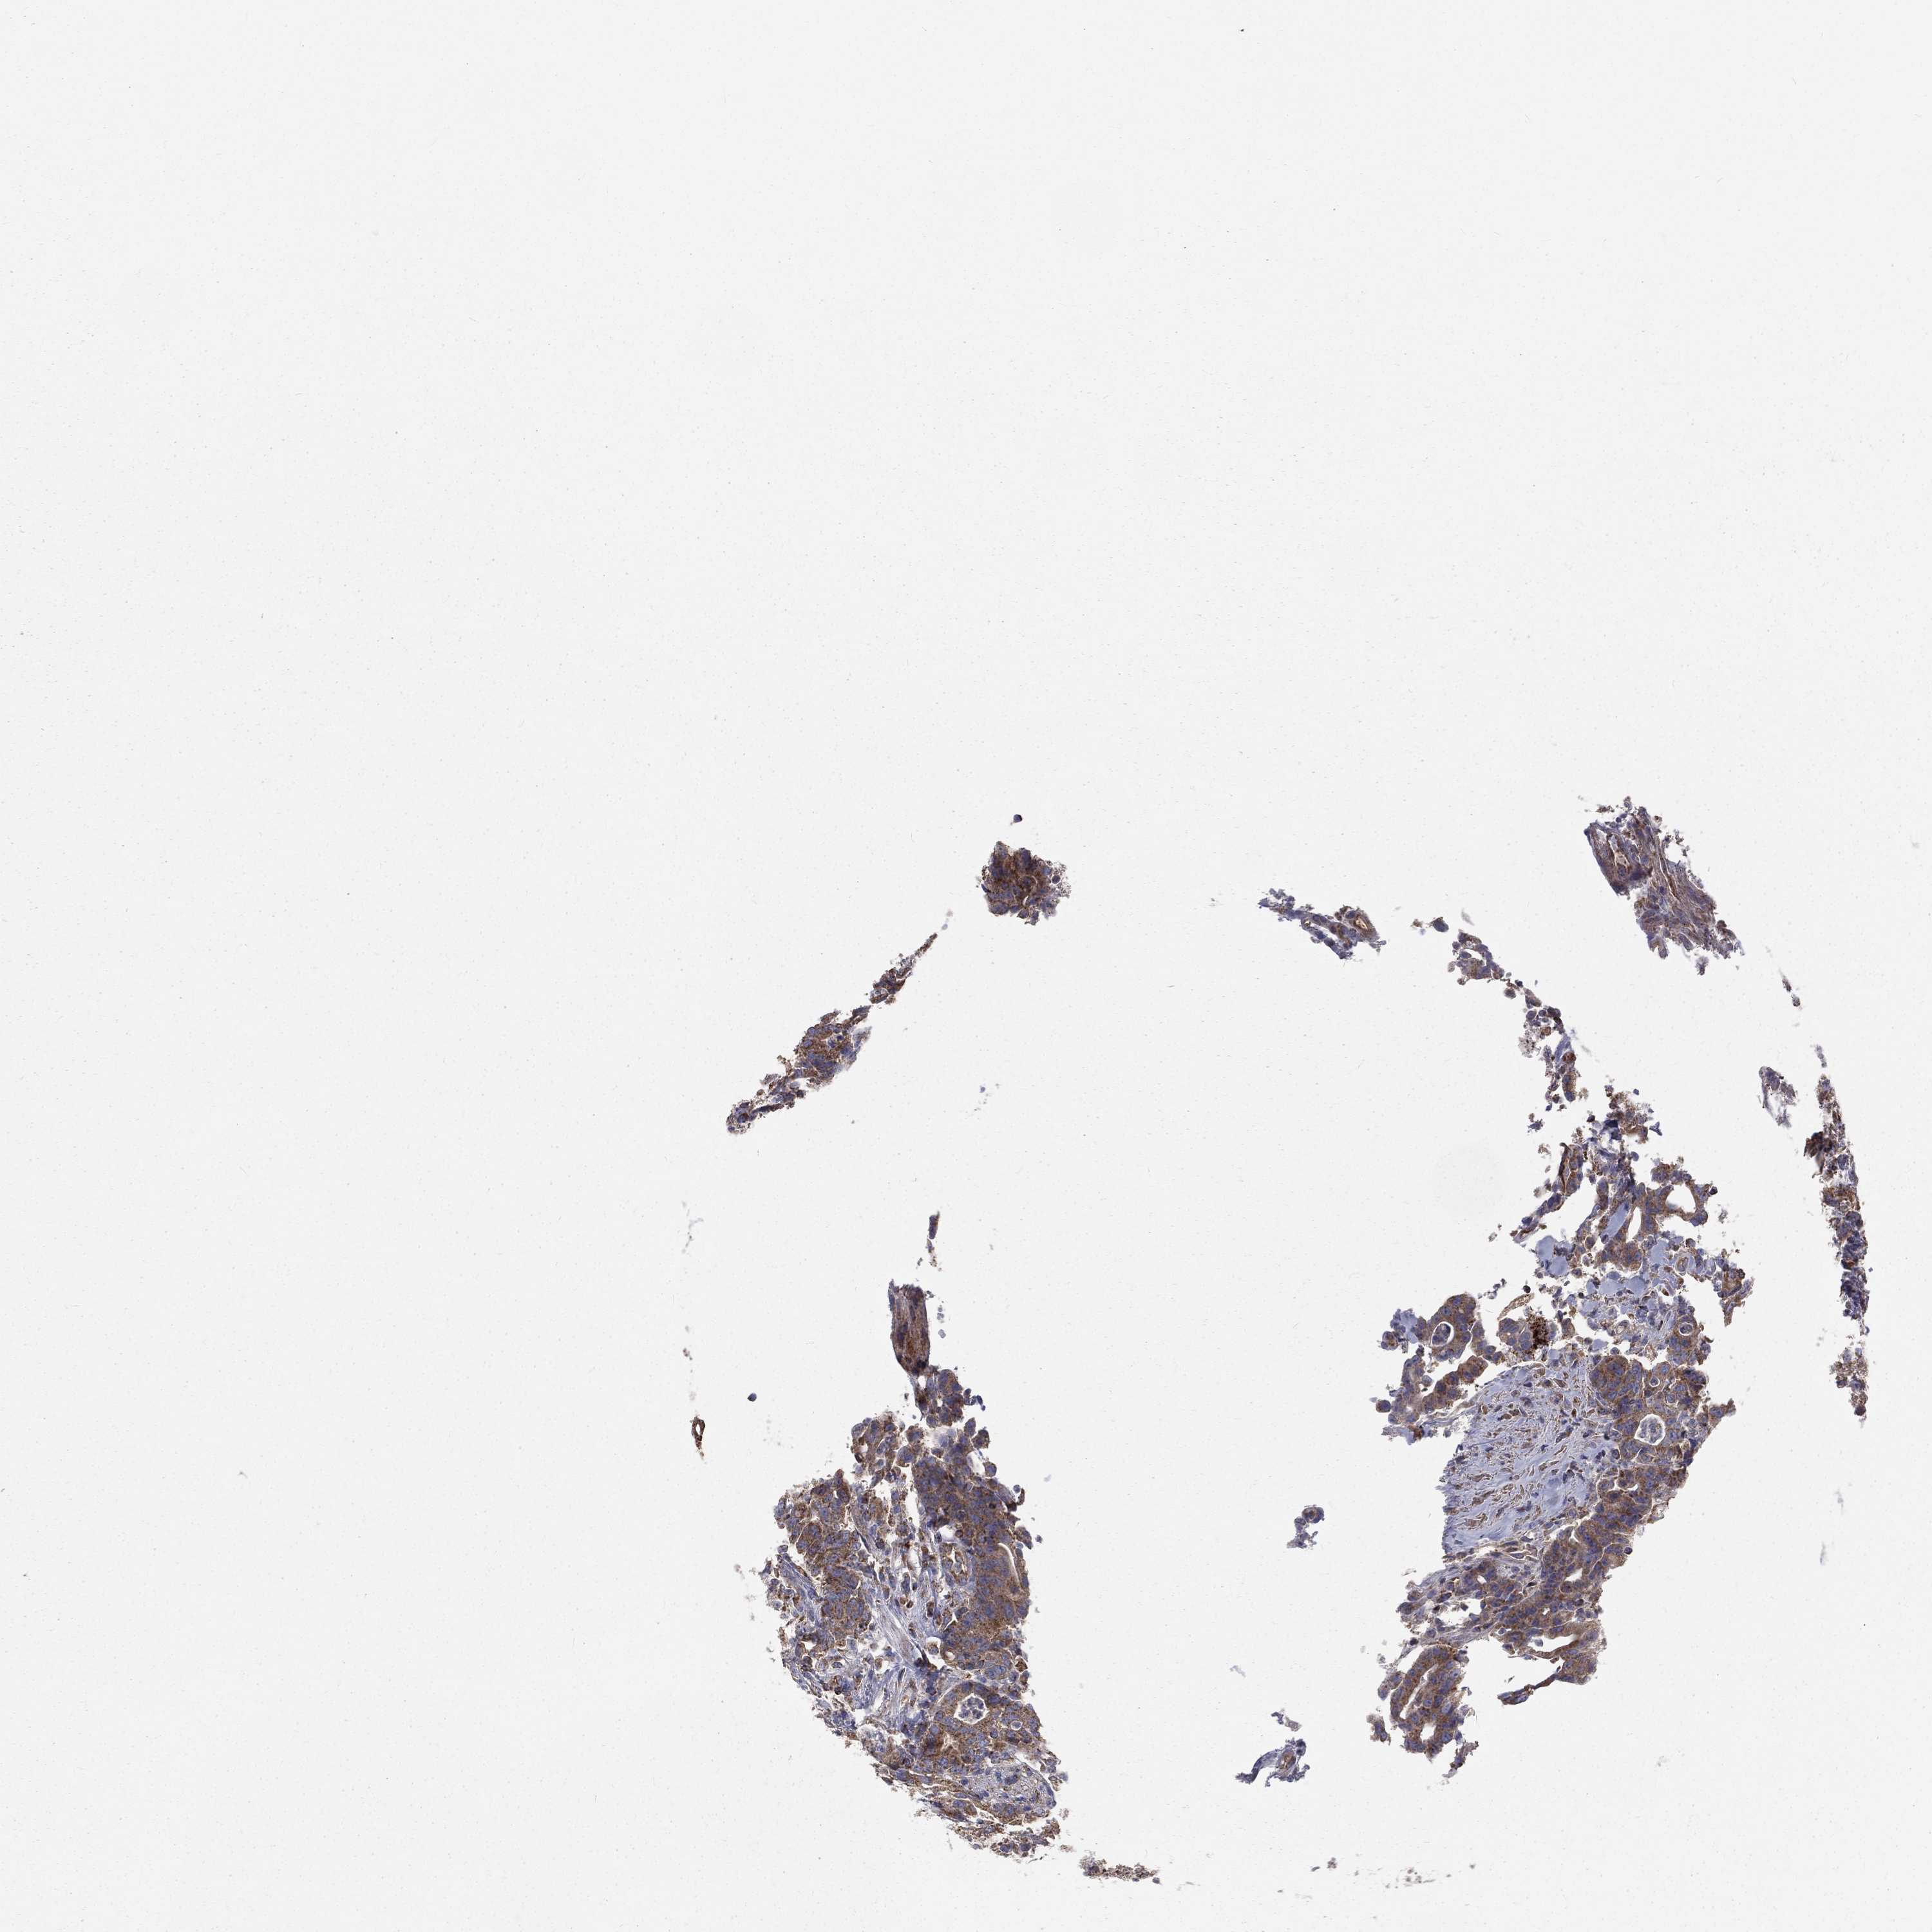

COLON ADENOCARCINOMA (VALIDATION) - Interactive survival scatter ploti

The Survival Scatter plot shows the clinical status (i.e. dead or alive) for all individuals in the patient cohort, based on the same data that underlies the corresponding Kaplan-Meier plots. Patients that are alive at last time for follow-up are shown in blue and patients who have died during the study are shown in red.

The x-axis shows the expression levels (FPKM) of the investigated gene in the tumor tissue at the time of diagnosis. The y-axis shows the follow-up time after diagnosis (years). Both axes are complimented with kernel density curves demonstrating the data density over the axes. The top density plot shows the expression levels (FPKM) distribution among dead (red) and alive patients (blue). The right density plot shows the data density of the survived years of dead patients with high and low expression levels respectively, stratified using the cutoff indicated by the vertical dashed line through the Survival Scatter plot. This cutoff is automatically defined based on the FPKM cutoff that minimizes the p-score. The cutoff can be changed by dragging the vertical line or by entering a cutoff value in the square labeled "Current cut-off".

Under the Survival Scatter plot the p-score landscape (black curve; left axis) is shown together with dead median separation (red curve; right axis). Dead median separation is the difference in median mRNA expression between patients who have died with high and low expression, respectively. It is calculated as follows: median FPKM expression of dead patients with high expression - median FPKM expression of dead patients with low expression. This is intended to aid the user in visually exploring custom cutoffs and the associated p-scores and dead median separation.

Individual patient data is displayed and can be filtered by clicking on one or more of the category buttons on the top of the page. Categories describing expression level and patient information include: high, low, alive, dead, female, male and tumor stages. The scale of the x-axis can be toggled between linear and log-scale by clicking on the "x log" button. Mouse-over function shows TCGA ID, patient information and mRNA expression (FPKM) for each patient.

& Survival analysisi

Kaplan-Meier plots summarize results from analysis of correlation between mRNA expression level and patient survival. Patients were divided based on level of expression into one of the two groups "low" (under cut off) or "high" (over cut off). X-axis shows time for survival (years) and y-axis shows the probability of survival, where 1.0 corresponds to 100 percent.

HADH is not prognostic in Colon Adenocarcinoma (validation)

Best expression cut offi

Based on the FPKM value of each gene, patients were classified into two groups and association between prognosis (survival) and gene expression (FPKM) was examined. The best expression cut-off refers the FPKM value that yields maximal difference with regard to survival between the two groups at the lowest log-rank P-value. Best expression cut-off was selected based on survival analysis .

When clicking on this number, the vertical dashed line indicating cut-off, the interactive survival plot, and the Kaplan-Meier curve will be adjusted to show results based on the best expression cut-off.

: 78.29

P scorei

Log-rank P value for Kaplan-Meier plot showing results from analysis of correlation between mRNA expression level and patient survival.

N/A

Average pTPM 63.7

Number of samples 486